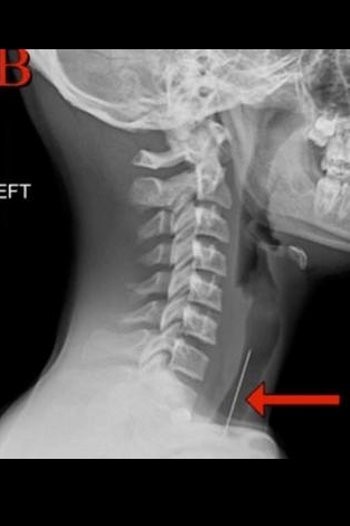

5. Kepala Tertusuk Tombak Pancing

Tombak menghujam tepat di atas mata kirinya dan mendesak otak. Beruntung tombak tidak mengenai titik vital dan dokter bedah dapat mengambil tombak tanpa merusak otak di kepalanya.